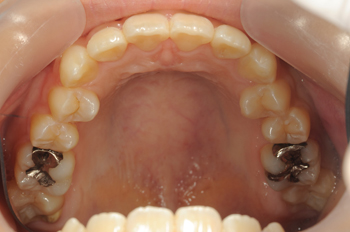

Before